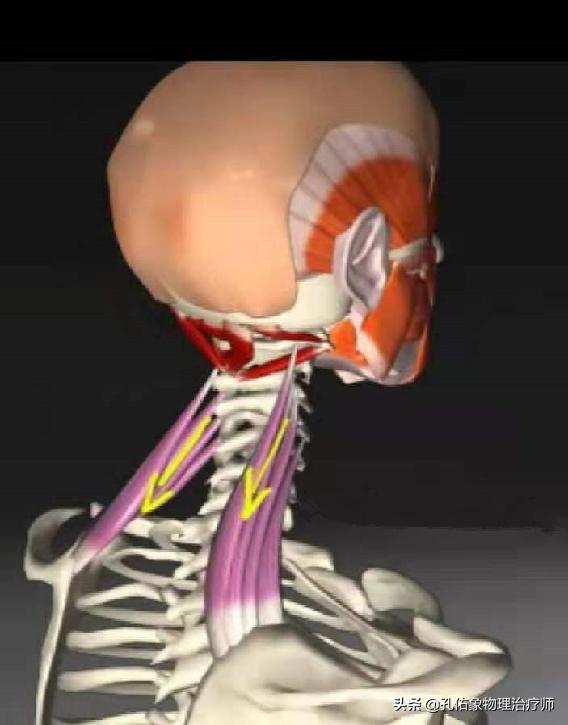

Comme indiqué ci-dessus, ce muscle est anatomiquement ce que l'on appelle un "levator scapulae (anatomie)". Il se développe d'une part sur l'apophyse transverse des vertèbres cervicales 1 à 4, et d'autre part à l'endroit même où se trouve le point douloureux (l'angle supérieur interne de l'omoplate). Sa fonction principale est la suivante :Lorsque la fin du point de douleur est fixéeLa tête et le cou sont inclinés vers l'arrière lorsque les deux côtés sont contractés et raccourcis.Lorsque la tête est baissée pendant une longue période, elle s'étire progressivement lorsque la tête est tirée vers l'avant, jusqu'à ce qu'à la limite, lorsqu'il n'est plus possible de l'étirer davantage, il y ait une douleur à l'angle supérieur interne de l'omoplate, à l'extrémité stationnaire.。